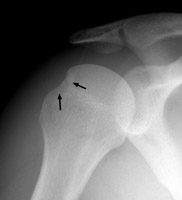

Hill-Sachs Sign

s/p anterior shoulder dislocation

Frontal film of the right shoulder which reveals a defect of the posterolateral aspect of the humeral head, consistent with a Hill-Sachs deformity. The Hill-Sachs sign represents deformity of the superior, posterior border of the humeral head and is typically a result of impaction of the anterior inferior surface of the glenoid labrum on the posterolateral aspect of the humeral head during dislocation.